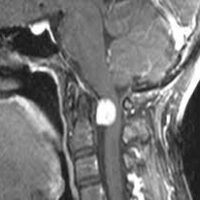

MR; omurganın primer tümörlerinin tanı ve değerlendirilmesinde tercih edilecek bir yöntemdir. Avantajları; yumuşak doku görüntülemesinin iyi olması, multiplanar görüntü elde edilebilmesi, nöral bası veya infiltrasyonun değerlendirilebilmesidir.